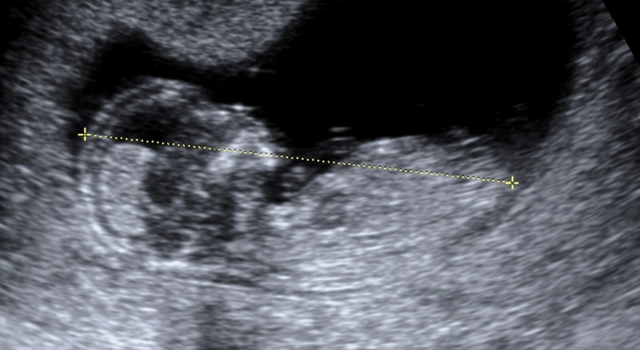

- la mesure de la clarté nucale du fœtus faite lors de l’échographie du premier trimestre qui a lieu entre la 11ème et la 13ème semaine d’aménorrhée.

En effet, avant la 14ème semaine les fœtus ont une poche de fluide sous la peau de la nuque visible à l’échographie. Le médecin mesure la taille de cette poche pour repérer un risque éventuel de trisomie 21 car les bébés atteints de cette pathologie ont une quantité de liquide plus importante.